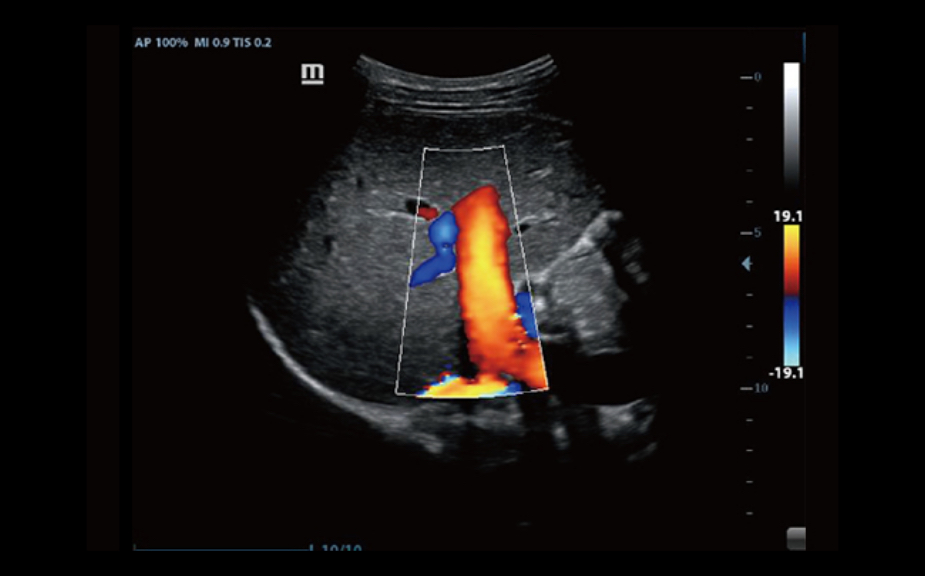

3B/4B G?rÞntÞleme

G?rÞntÞnÞn her y?nden h?zl? ve kolay bir ?ekilde izlenebilmesini sa?layan 3B/4B ?evirme ve E?itleme ?zelli?i ile